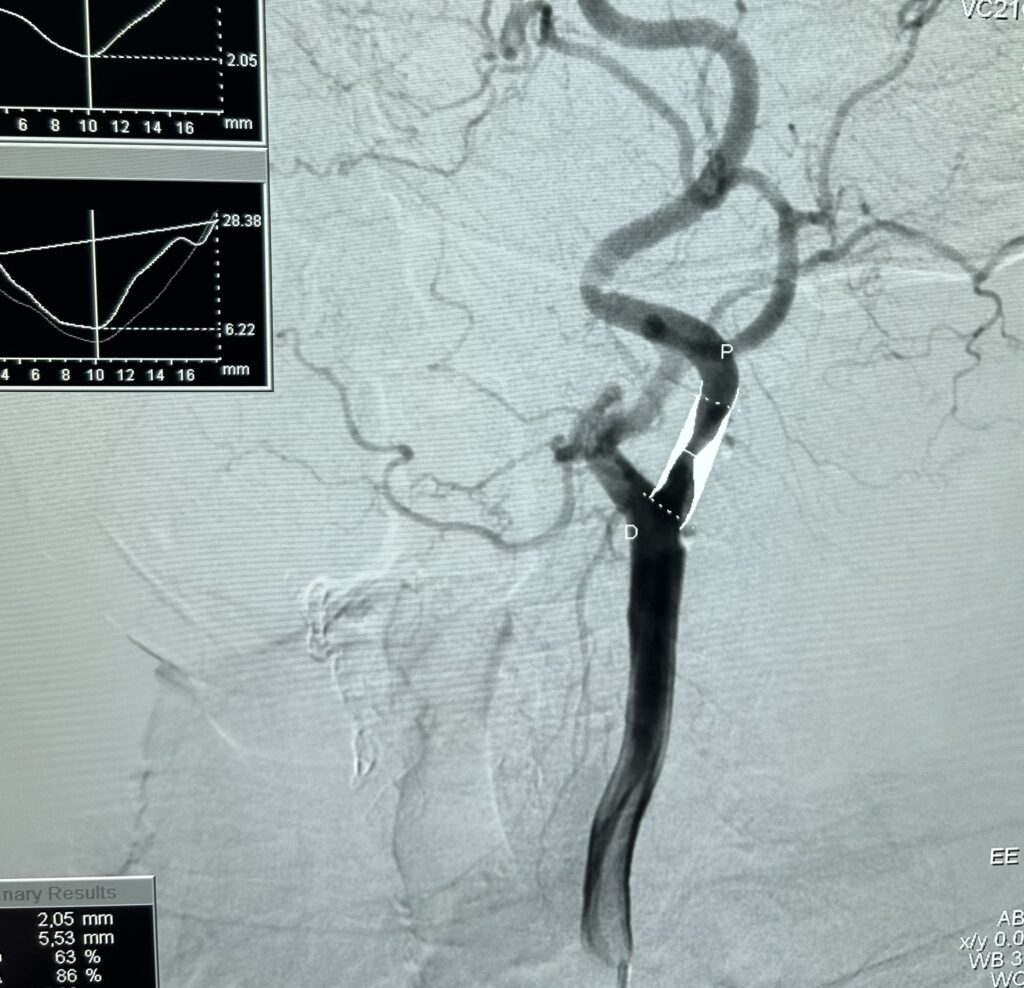

• Tratamento endovascular do aneurisma e dissecção das aortas torácica e abdominal.

Com o avanço constante dos materiais, equipamentos e técnicas, os procedimentos endovasculares tornaram-se cada vez mais seguros, eficazes e personalizados, podendo ser aplicados em diferentes doenças vasculares — desde obstruções arteriais e aneurismas até malformações e tromboses.